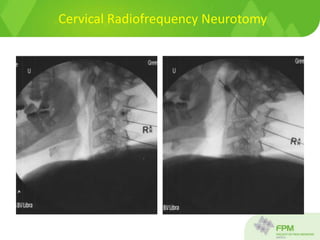

Cervical radiofrequency neurotomy

Position for C2/3 and C3/4 facet joint

Cervical radiofrequency neurotomy –

lateral view

Marker shows needle at C2/3 facet joint